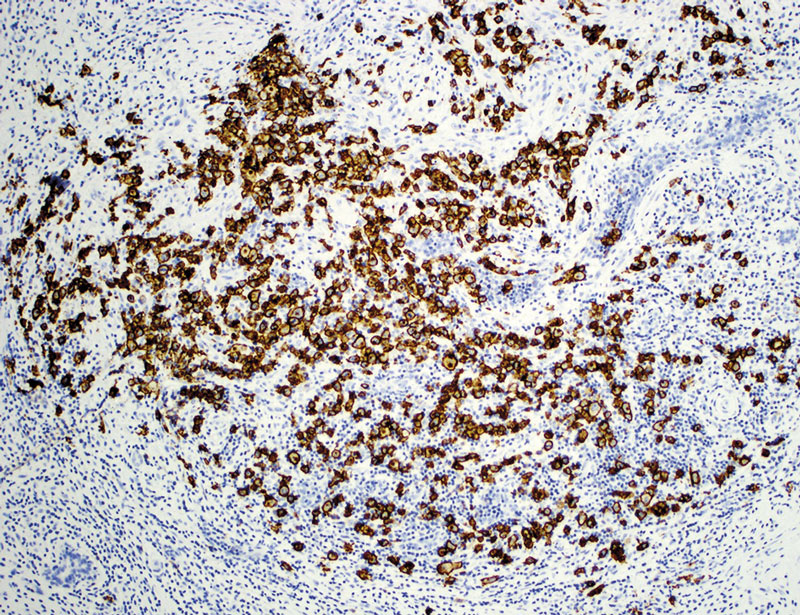

Figur 3. Mikroskopibild av implantatkapsel med CD30-positiv immunhistokemi. Bilden visar ett kluster av celler vilka aggregerar i en massa.